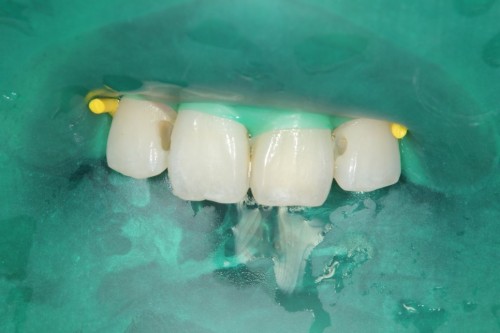

前歯の虫歯です。唾液の量が多い方や歯ぐきから出血がある方にはラバーダム防湿法を使います。このように緑色のゴムのシートを使用して、歯に唾液や血液が付かない様にします。

虫歯をとったところです。

無事治療が終わりました。削った穴に唾液や血液が入り込むと接着力が低下してしまいます。今回、削った穴に汚れが付く事無く、審美的な治療が出来ました。

ダイレクトボンディング

費用2万円×2本

リスクとして変色や欠ける可能性がある(修復可能)。